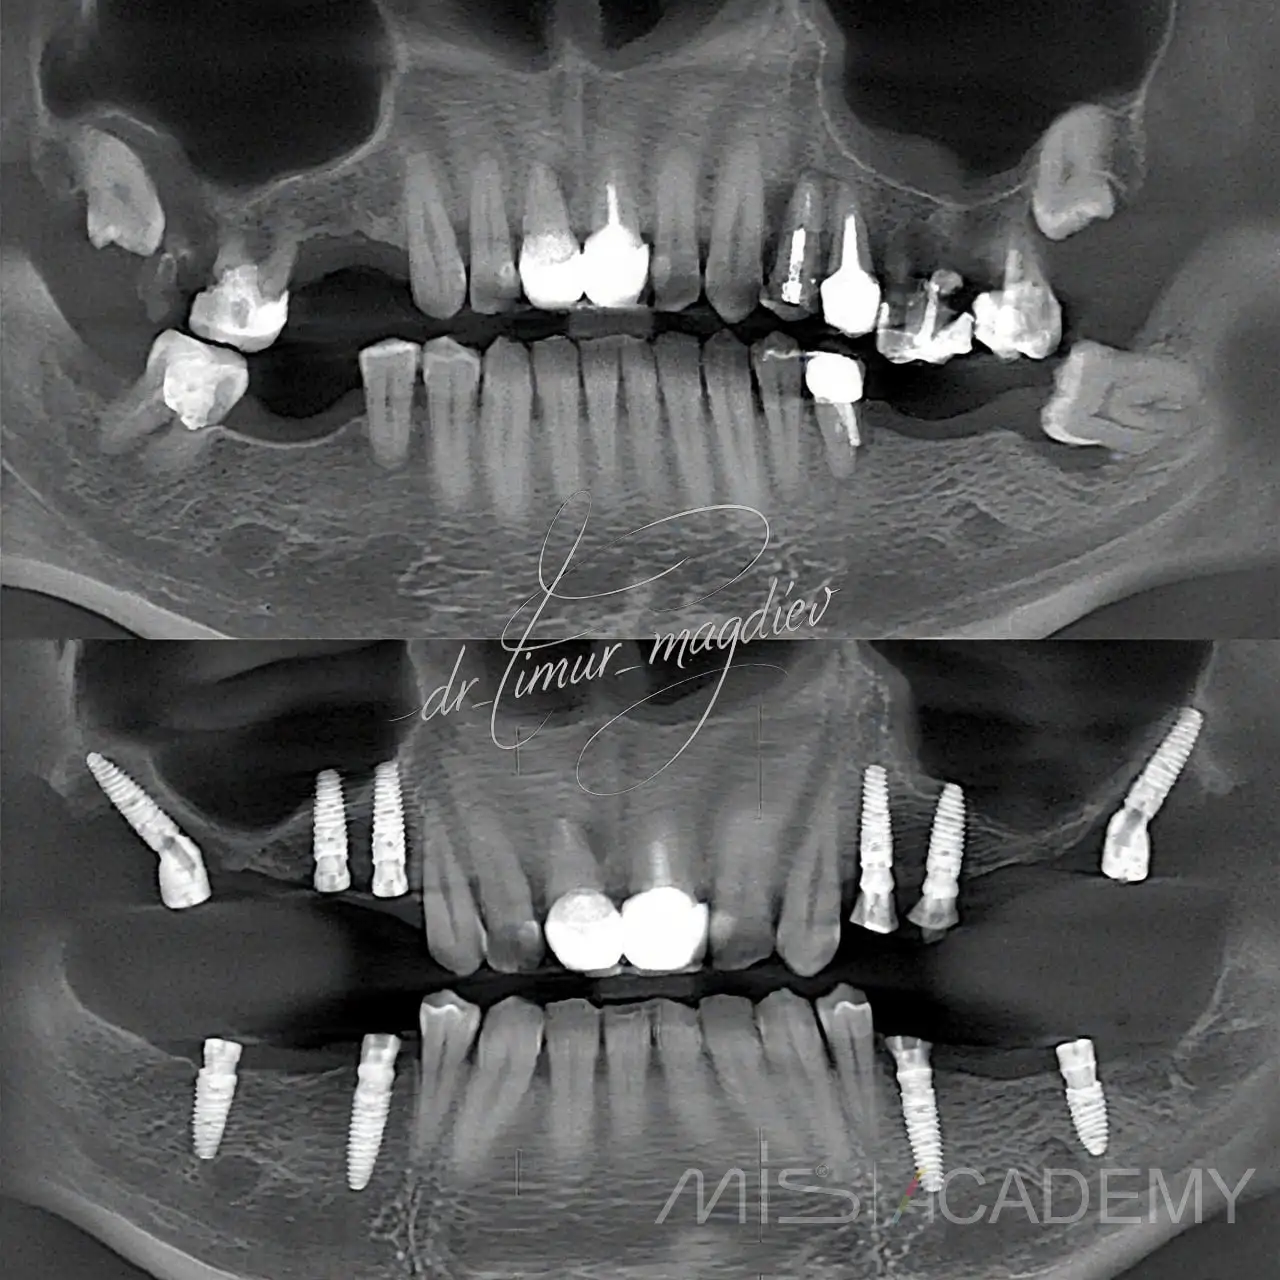

Клинический случай:

Восстановление жевательных Зубов.

— Установка имплантатов MIS C1.

— MU.

— Connect.

— Обошли синусы с помощью угловой расстановки имплантатов.

— Протезирование циркониевыми коронками.